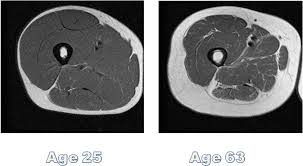

You can gain 15 lbs of fat and lose 15 lbs of muscle without even realizing because your body weight stays the same and this happens in your 30’s! Bottom line technology has made calories easy to get and physical strength easy to forget.